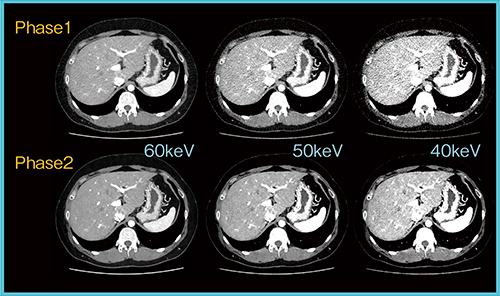

4.Spectral Imaging System

キヤノンメディカルシステムズの新しいDual Energy技術であるSpectral Imaging Systemは現在,phase1からphase2へと改良が加えられている。Spectral Imaging Systemでは,仮想単純X線画像,Virtual Non Contrast(VNC)画像,Iodine Map,Spectral HU Curveなどが取得できる。

Spectral Imaging Systemは,高低2種の管電圧を高速で切り替える“Rapid kV Switching”で2種類のエネルギーデータを収集するSpectral Scanと,切り替えで生じるデータ欠損部分をDeep Convolutional Neural Network(DCNN)で補間・復元するSpectral Reconstractionから構成される。図4は,Spectral Imaging Systemの画質をphase1とphase2で比較したものだが,ハードウエアを更新せずにディープラーニングの学習の高度化だけで,大きく改善されていることがわかる。これはディープラーニング技術の特徴でもあり,今後もさらなる改善の可能性が期待できる。

図4 ディープラーニングの学習の更新による画質改善

Spectral Scan(135-80kV),AEC:162〜266mAs(0.5s/r),FOV:L,PF0.812,12.5mGy